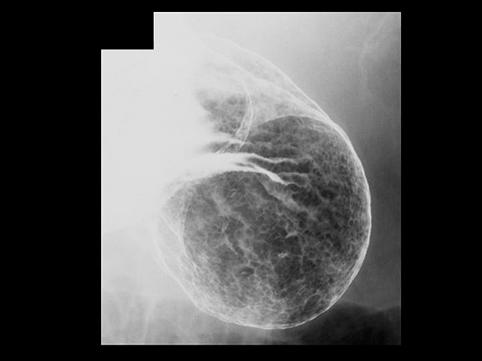

疾患(病理主体)の分類悪性上皮性腫瘍/腺癌

部位(臓器別)胃(部位)/2つ以上

検査方法X-P

腫瘍の肉眼分類0型(表在型)/IIb型(IIb+IIa)

病変の最大径(ミリ)40以上

腫瘍の深達度m